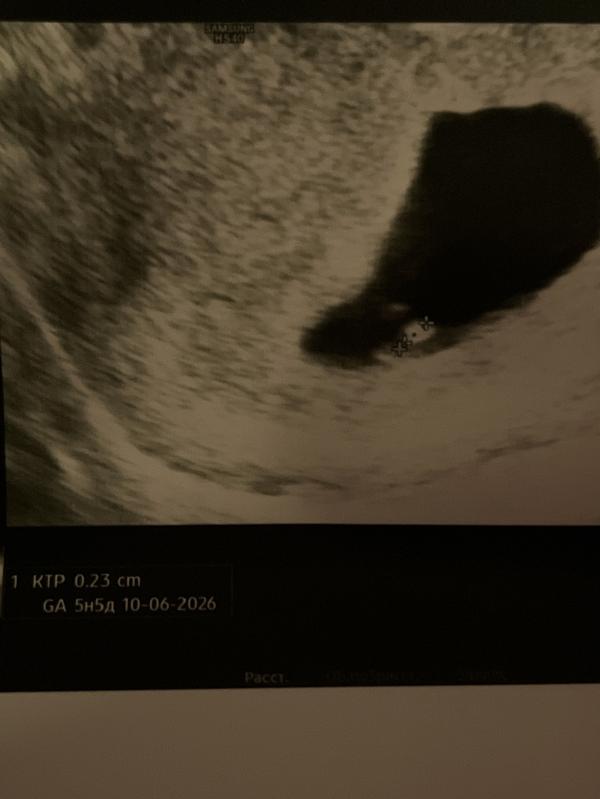

Живой эмбрион, сердечко бьётся😻

Срок ставят 5 недель и 5 дней

Сердечко не дали послушать, лишь показали пульсацию. Он такой маленький 🙌